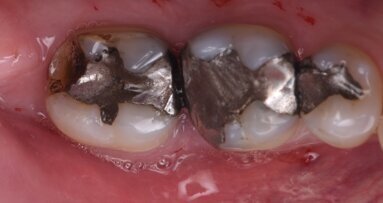

Dr Labanca, more and more general dental professionals are performing dental implant therapies, and treatment times and healing times are increasingly being reduced. In your opinion, are we moving backwards rather than forwards in dental implantology? You have pointed out a very important issue. My feeling is that we are facing a time in society in which we expect to receive everything we need immediately. Patients and dentists imagine that biology can also follow these rules. This is, of course, a huge mistake, which quite often results in failure. Too often, I hear proposals that are more about marketing rather than medicine. We must go back to the fact that we offer clinical solutions; we are not selling implants! And if we have to wait a little bit longer for a better long-term result, this better result will always justify our decision.

Absolutely, yes. In the past, we were used to waiting a long time to obtain results that were truly based on evidence. Now, we are moving to adopt new clinical procedures or new products too fast and not taking the required time to verify their long-term reliability.